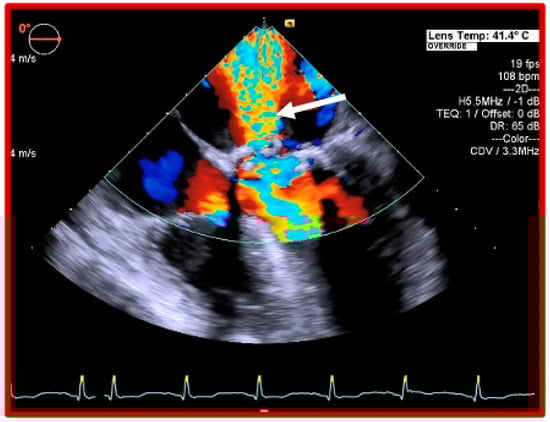

Early Basal Cuspal Tear of a Porcine Bioprosthetic Mitral Valve Causing Massive Mitral Regurgitation